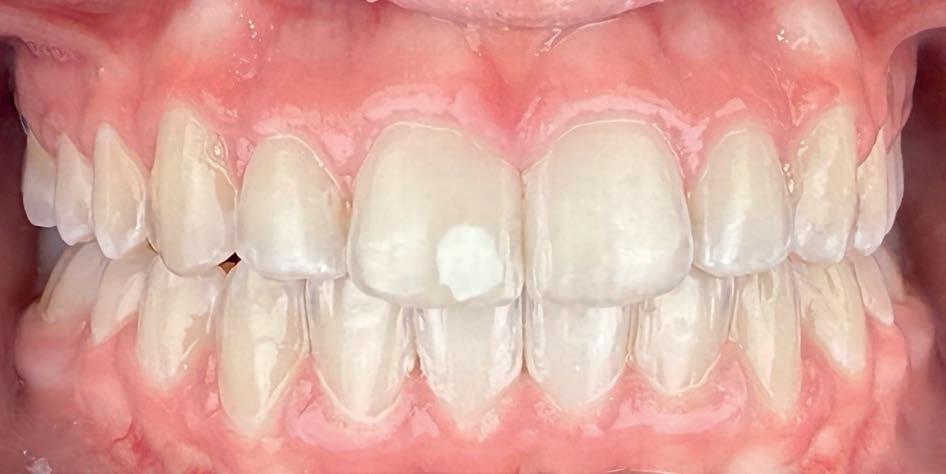

Bij onvoldoende mondhygiëne

Wanneer er sprake is van onvoldoende of slechte mondhygiëne, is gezamenlijke aanpak noodzakelijk. Denk aan zichtbaar plaque, gingivale zwelling of beginnende witte vleklaesies. In zulke gevallen intensiveren wij de instructie en evalueren we de motivatie en mogelijkheden van de patiënt. Soms stellen we de start van de behandeling uit, of plannen we extra controles in.

Daarnaast adviseren wij om de tandarts of mondhygienist tijdelijk vaker in te schakelen — bijvoorbeeld elke 3 maanden — om professionele reiniging en begeleiding te bieden. Op die manier kan de mondsituatie worden gestabiliseerd voordat er verdere orthodontische stappen worden gezet.